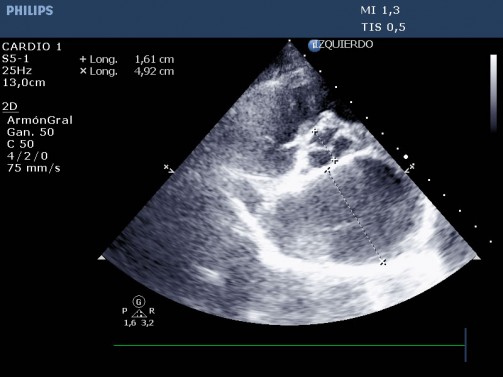

Imagen 2 – Congestión hepato-venosa marcada.

Se observa que el paciente está en fibrilación atrial. Así que se realiza una ECOFAST para valorar causa y se recomienda hospitalizar en clínica de 24h con servicio de cardiología para estabilizar al paciente antes de acabar el estudio.

Las imágenes y videos obtenidos son compatibles con insuficiencia cardíaca en estadio C (ACVIM 2009) por estenosis mitral congénita con hipertensión pulmonar moderada y fibrilación atrial.

Imagen – Gran dilatación de la aurícula izquierda cardíaca ( AI/Ao 3,06)

Doppler color en VM en corte apical izquierdo de 4 cámaras

Estenosis mitral congénita con cambios compatibles con existencia de hipertensión pulmonar. Además, el paciente presentaba fibrilación atrial, por lo que se le aconsejó estabilizar mediante hospitalización.